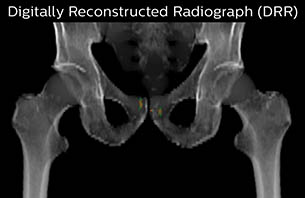

Using the mDIXON and 3D bFFE images, the RT planner marks the position of the nickel-titanium fiducial markers, and contours are transferred to the digitally reconstructed radiographs (DRRs). Reference image matching is based on these markers. “In the rare cases, where visualization of the fiducial markers fails, we do a CT to confirm their location,” Dr. Keyriläinen notes.

MR-only simulation workflow The 3D T1W FFE mDIXON sequence provides in-phase, water and fat images in one acquisition. Target and organs-at-risk are delineated on the 3D T2W TSE images. Prostate GTV is shown in orange, PTV in purple. The 3D bFFE sequence is used by the planner to mark the position of the fiducial markers (gold anchors) and contours are transferred to the digitally reconstructed radiographs (DRRs).

The Philips MRCAT approach for an MR-only based dose planning provides CT-like density information calculated from MR images for dose calculations, as well as high contrast anatomical T2W images for target delineation. [2-3] The MRCAT images with density information are DICOM conform and can be automatically exported to treatment planning systems (TPS) as primary image dataset for dose calculations and to generate MR-based digitally reconstructed radiographs (DRRs).